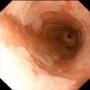

Feto cara cara2 Feto Oreja manos carita bebe Barret Barrett1 Pólipo Diverticulos Cancer rectal Transverso Duodeno Rayos%20x.jpg